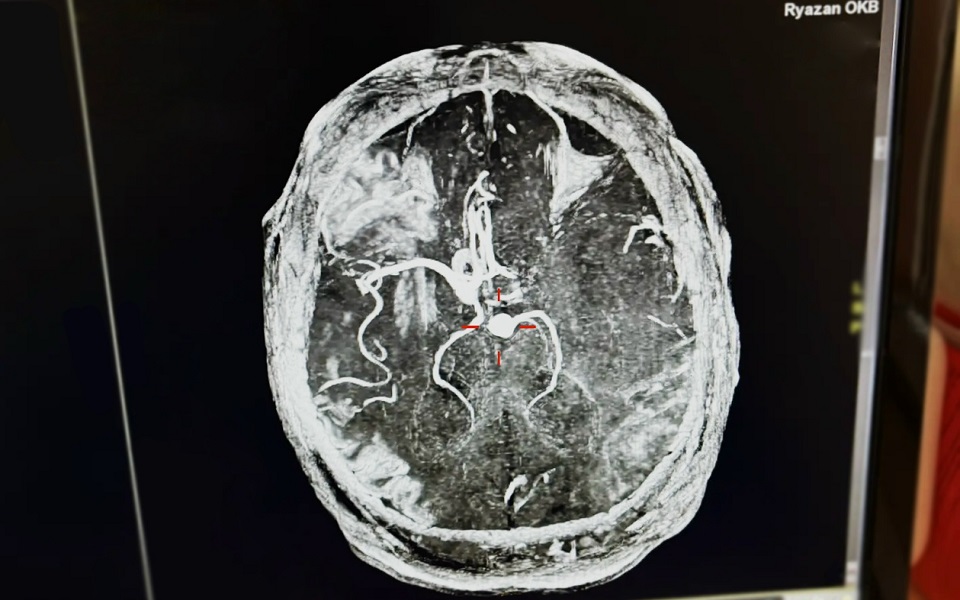

Рязанские врачи спасли 43-летнего рязанца с инсультом. О сложном случае рассказали представители минздрава региона.

"Ему измерили давление, и результаты оказались шокирующими — 265/155, что свидетельствовало об опасном гипертоническом кризе", - рассказали в минздраве. Диагностировали инсульт.

Тромб сумели устранить, а когда начали выяснять, что могло привести к развитию инсульта, поначалу не обнаружили типичных причин: пациент не пил и не курил, не имел предрасположенности или патологий. Затем жена рассказала о его привычке выпивать ежедневно 7-8 банок энергетических напитков. Муж говорил, что ему нравится их вкус.

Иллюстрации:  минздрав Рязанской области